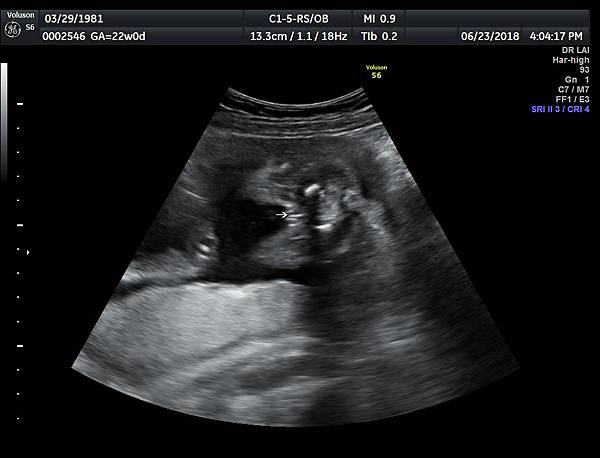

今天下午一位28歲第一胎的孕婦來診所做超音波檢查,之前他們一直認為懷的是女兒(檢查前資料顯示胎兒是女生);今天我的診斷胎兒是男生,但是懷疑有尿道下裂的問題(附圖 1~4),我的建議是抽羊水做染色體基因檢查,除了確定性別之外,也可以排除是否合併基因異常。

尿道下裂的個案,產檢時常被看成女生,所以做高層次檢查時一定要看清楚胎兒性別,即使父母表明不要知道胎兒性別,我一樣要看清楚性器官,只要不主動告知父母胎兒性別即可,這樣的堅持就是要排除尿道下裂;女寶寶的特徵是典型三條線(附圖 8.),男寶寶需要看到突出的生殖器(附圖 9.)。

診斷尿道下裂常用的鬱金香sign(tulip sign)(附圖 10.11.),它的特徵就是龜頭陷入陰囊中間,胎兒如果是男生,一定要看到龜頭離開陰囊,這樣就沒有問題,每次遇到尿道下裂的個案時,我都會有一個感觸,男生如果能站著尿尿都要很感恩。